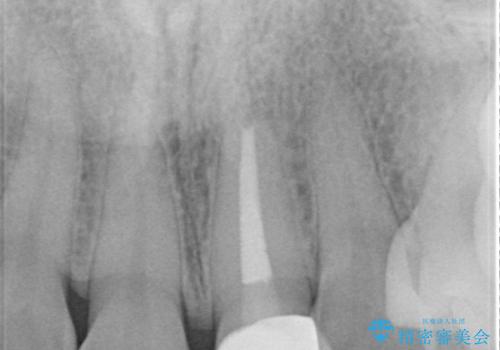

- 他院で前歯の変色をダイレクトボンディングにて修復治療しておりましたが、審美障害を主訴に来院されました。

根管治療後、オールセラミックにて治療を行っております。

根管治療の注意事項(リスク・副作用など)

- 根管治療により類似の全ての症例の問題が解決するわけではなく、症例はあくまでも一例です

- 根管治療により痛みや腫れがひかない事や、術後に痛みや腫れが生じる事、治療によるファイル破折やパーフォレーションなどの偶発症、術後の歯根破折を生じる可能性もあります